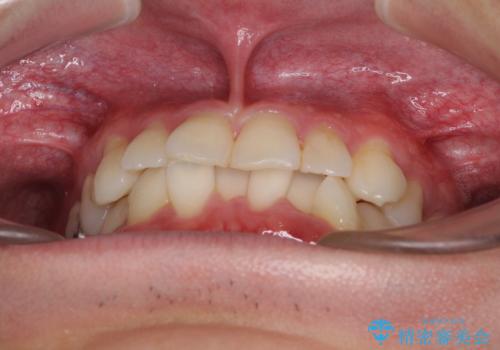

- 30代男性

- 矯正装置

- 審美装置

- 治療期間

- 1年2ヶ月

- 右下奥歯の虫歯がしみて痛いとのことで来院された患者様です。

神経近くにまで及ぶ大きな虫歯でしたが、速やかに処置を行い、痛みは即日解消されました。

虫歯が大きかったため、クラウンによる補綴治療が必要になる旨をお伝えしたところ、矯正治療にも興味があるとのことでした。

短期間で手間のかからない方法がご希望でしたので、ワイヤー装置による矯正治療を行うこととし、矯正治療後に右奥2歯をセラミッククラウンにて補綴することとしました。